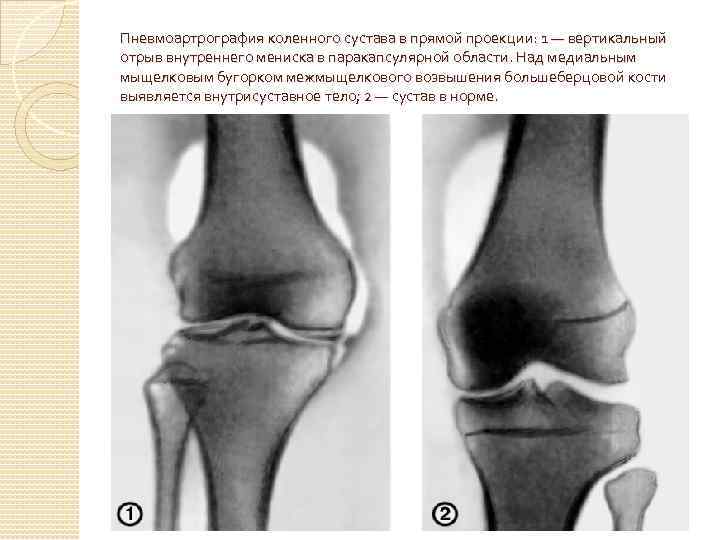

Рентгенонегативные средства ПРИМЕНЕНИЕ: 1. Контрастирование пищевода, желудка, двенадцатиперстной и толстой кишки самостоятельно или в комплексе с рентгенопозитивными РКС(двойное контрастирование) 2. Рентгенография крупных суставов (пневмоартрография) 3. Цистография — рентгеноконтрастное исследование мочевого пузыря 4. Больным с непереносимостью йодированных РКС.

Пневмоартрография коленного сустава в прямой проекции: 1 — вертикальный отрыв внутреннего мениска в паракапсулярной области. Над медиальным мыщелковым бугорком межмыщелкового возвышения большеберцовой кости выявляется внутрисуставное тело; 2 — сустав в норме.